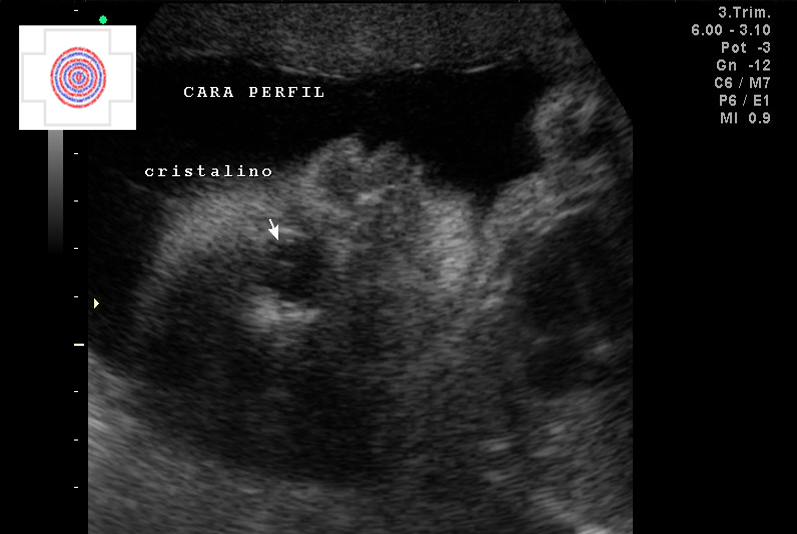

3D SUPERFICIAL PERFIL CARA